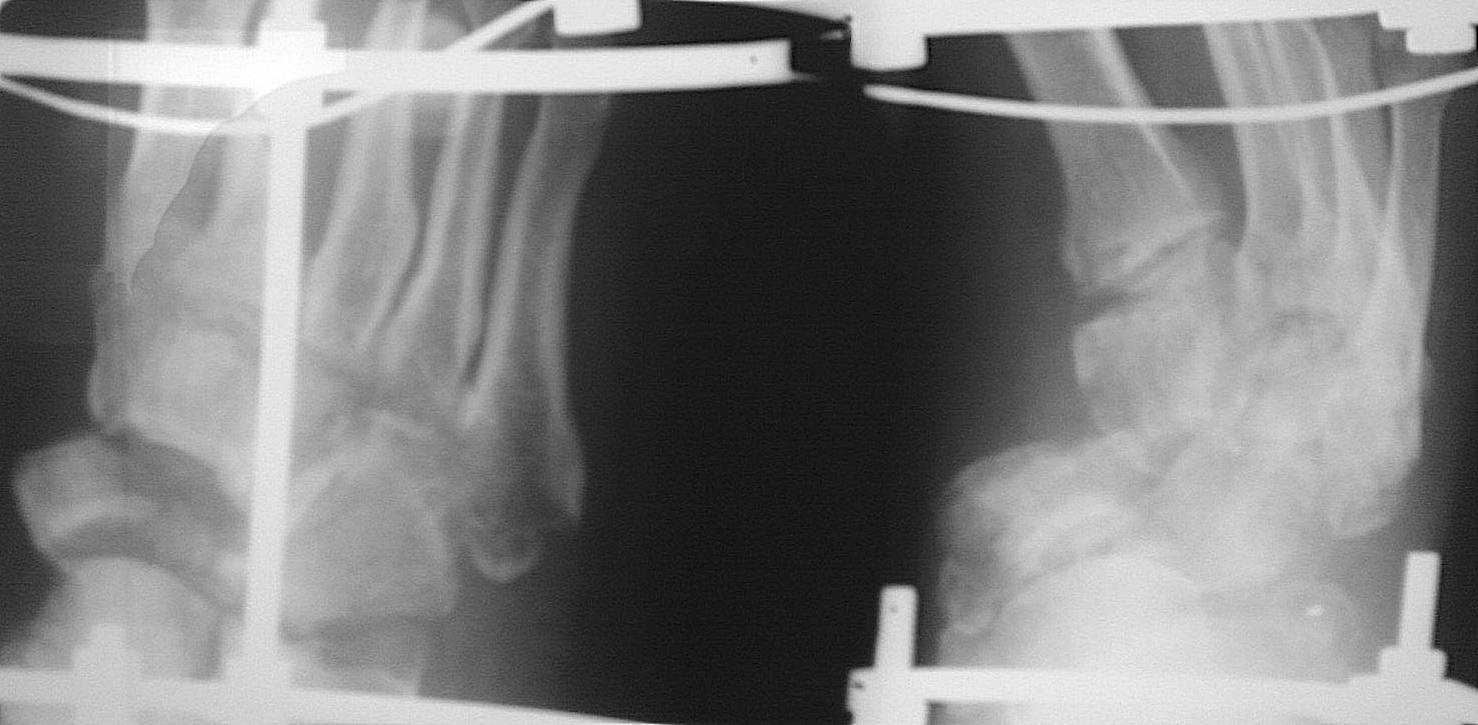

[Ortho] застарелый переломовывих в суставе Шопара

Обратился пациент 40 лет через 2,5 мес после травмы,

не курит, социален. Первым этапом наложили дистрактор, дозированная

дистракция, вторым этапом планировали репозицию ладьи с bridge plate

(шейка - клин). После выходных обнаружили такую картинку некрозов,

доступ планировался именно так. Считаю, что основная проблема в

ладье. Фрагмент ладьи абс неподвижен. Вопросы: стоит рисковать или нет?

будет ли менее рискованная операция позже по рубцу? Что еще следует

учесть (возможно недопонимаю анатомию повреждения)? Другие варианты?